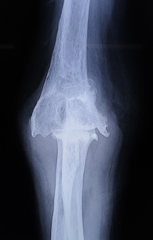

3. 肘の外傷

肘の骨折や靭帯損傷はときに治療が困難であり、専門医による治療が必要となることがあります。状態により前方、後方、側方のアプローチを使い分け、また術中エコーも併用しより正確な整復を心がけています。